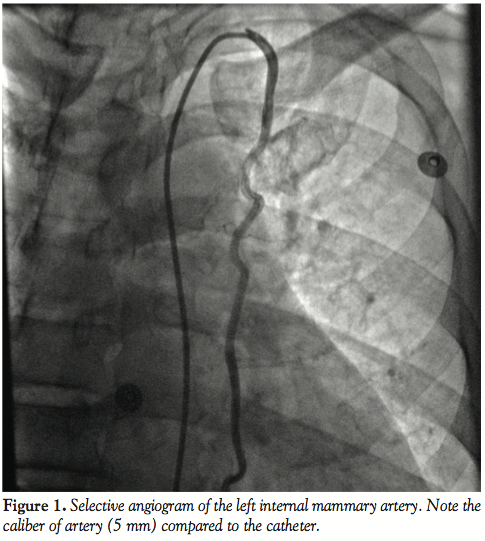

The utilization of internal thoracic arteries for coronary revascularization is well established and preferred to ensure prolonged graft patency. We report a case of a 55-year-old male who had undergone coronary artery bypass graft surgery (CABG) using only venous grafts to the left anterior descending (LAD) and first diagonal coronary arteries. The left internal mammary artery (LIMA) was not used due to extensive collateral formation from the left internal thoracic via superior and inferior epigastric arteries to the left femoral artery compensates the chronically occluded left common and external iliac arteries. Selective angiogram of the LIMA demonstrated it to be larger than normal (5 mm). The caliber is considerably larger than usual (≥3 mm). Further interrogation demonstrated it to be collaterals to the left common femoral artery via the epigastric arteries.

Imaging of the right coronary and circumflex arteries revealed no significant lesion. The left ventricular ejection fraction was normal. The injection into the LIMA showed marked increased diameter (Figure 1) with unusually long collaterals extending to the left common femoral artery (Figure 2). There was a total occlusion of the left common femoral artery (Figure 3) with reconstitution of the common femoral artery from the LIMA collaterals (Figure 4). There was no evidence of coarctation in the proximal ascending aorta identified of the aorta on this or prior coronary angiography studies (Figure 5).

In our case the unusual caliber (5 mm) of the LIMA and its collateralization of the left common femoral artery via the epigastric artery pathway is worth documentation. This condition may be rare, but it is important to realize that such an unusual collateral pathway may be present in cases in which ordinary abdominal aortography and pelvic runoff does not reveal any obvious collaterals compensating an occluded iliac artery.